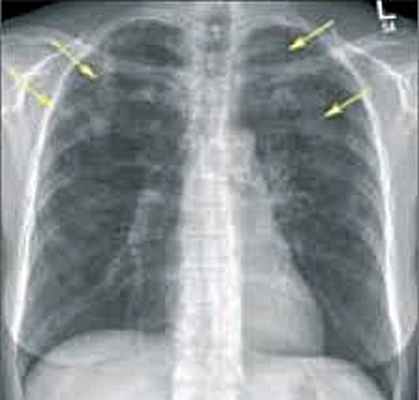

Специальные исследования • Рентгенограмма органов грудной клетки — мигрирующие транзиторные лёгочные инфильтраты, небольшой плевральный выпот • Биопсия лёгких.

- Рентгенография легких. На снимках видны субплеврально расположенные одиночные (реже множественные, двусторонние) нечеткие затемнения средней интенсивности неправильной формы размером до 3-4 см. В окружении инфильтрата легочный рисунок усилен, тень корня легкого слегка расширена. Характерна быстрая динамика инфильтратов с миграцией по легочным полям и исчезновением не позднее 1-2 недель после обнаружения (чаще через 1-3 дня) без остаточной рубцовой деформации. При длительно поддерживающемся инфильтративном воспалении в ткани легких могут образоваться фиброзные очаги и кистозные полости.